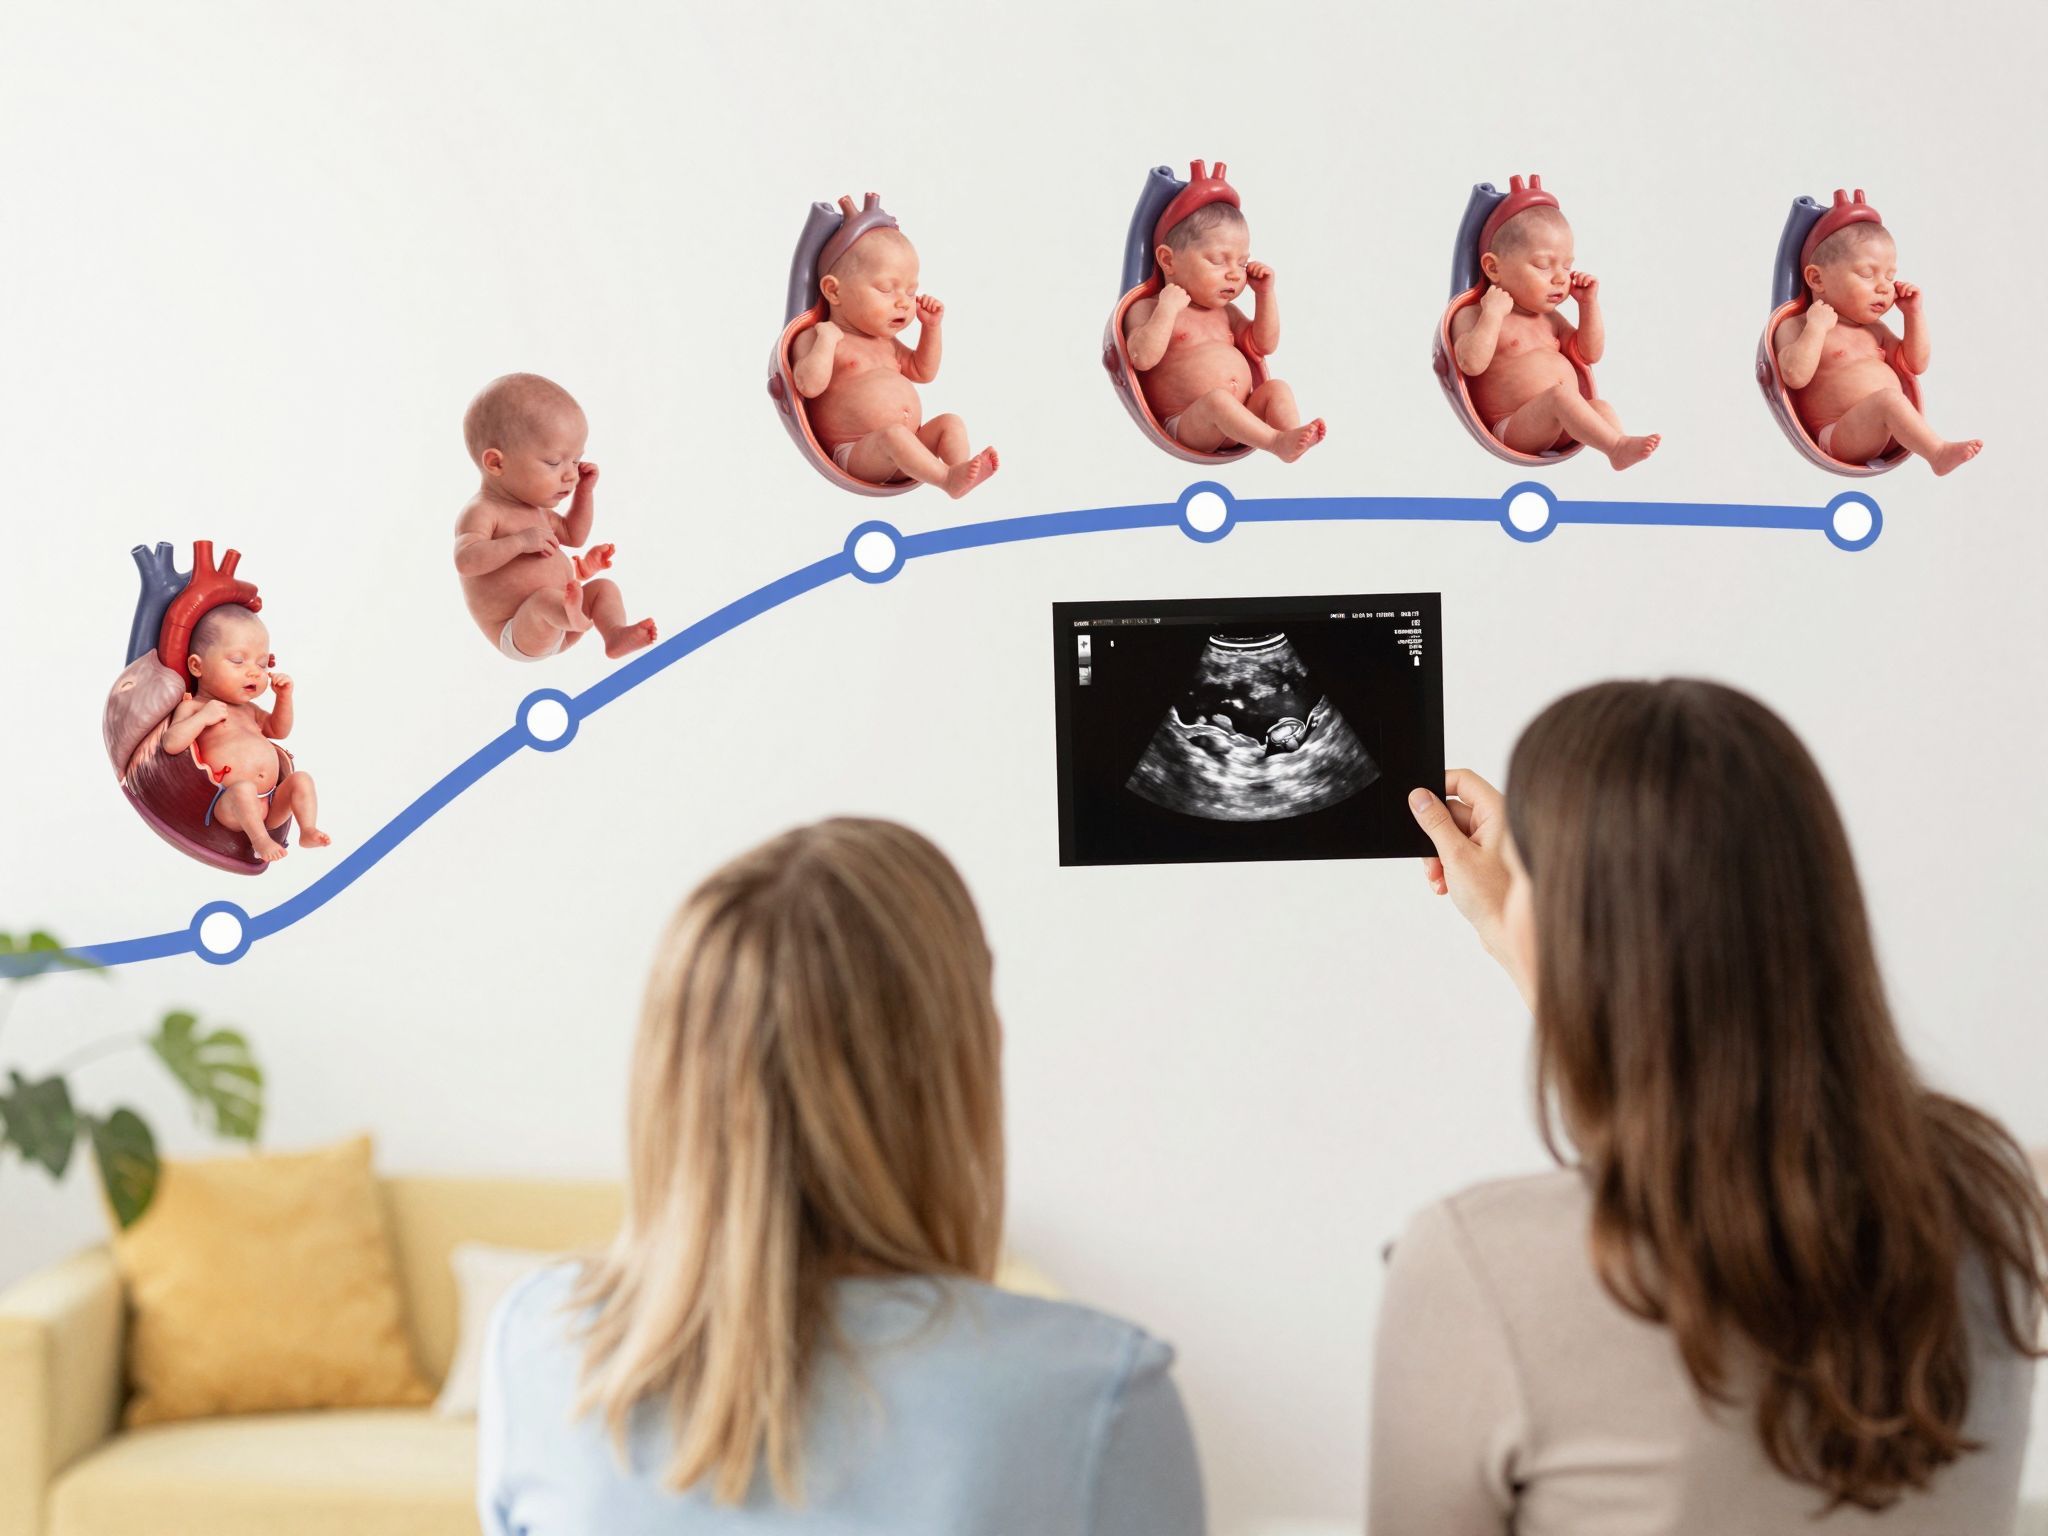

Amikor először fekszünk fel az ultrahang vizsgálóasztalra, a szívünk a torkunkban dobog. Nem csupán az izgalom miatt, hanem azért is, mert tudjuk: a monitoron feltűnő apró, vibráló pont jelenti a legfontosabbat. A magzati szívhang az élet első, hallható bizonyítéka, egy ritmikus ígéret, mely minden szülő számára a terhesség legmeghatározóbb pillanata. Bármennyire is modern és bonyolult a technológia, amit az orvos használ, a lényeg egyszerű: vajon jól van-e a baba? Vajon egészségesen dobog-e a szíve? Az ultrahang felvételek és leletek tele vannak szakmai rövidítésekkel – FHR, GA, CRL –, amelyek közül az egyik leggyakrabban felmerülő kérdés az FS rövidítés jelentése. Lássuk, mit árul el ez a néhány betű, és hogyan segít az orvostudomány abban, hogy a terhesség 9 hónapja a lehető legnagyobb biztonságban teljen.

A magzati szívfejlődés részletes idővonala

Ahhoz, hogy megértsük, mit lát az ultrahang, érdemes végigtekinteni, hogyan alakul ki a magzat szíve. Ez a folyamat rendkívül gyors és komplex, a terhesség első 8-10 hetében lényegében befejeződik a szívkamrák és főbb erek kialakítása.

Az első trimeszter: A struktúra építése

4–5. hét: Megkezdődik a szívcső (primitive heart tube) kialakulása. Ez az egyszerű csőkezdemény már képes az első, lassú összehúzódásokra.

6. hét: Megindul a szív elfordulása és kettéválása. Két kamra és két pitvar kezdi formáját ölteni. Ekkor már általában hallhatóvá válik a szívhang.

7–8. hét: A szeptumok (válaszfalak) kialakulnak a pitvarok és kamrák között. Ekkor kezdenek fejlődni a billentyűk is, amelyek biztosítják a vér egyirányú áramlását.

10. hét: A szív négy üregű szerkezete lényegében kialakult, bár a szív mérete még alig éri el egy borsószem nagyságát. Ekkor már a főbb erek, mint az aorta és a tüdőartéria is felismerhetőek.